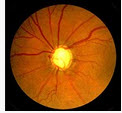

视神经萎缩(如图)的治疗包括以下哪些()

A:病因治疗

B:禁烟酒

C:复方丹参

D:维生素B族类

E:针灸